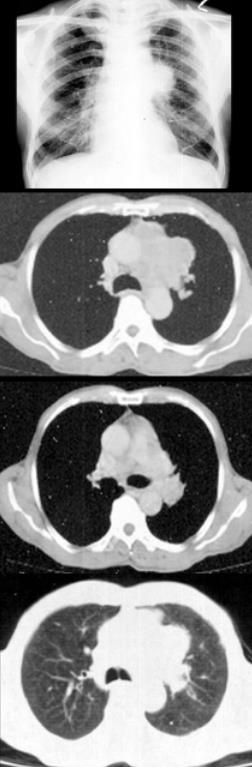

患者60岁,男,有长期吸烟史,左声带麻痹、声音嘶哑2个月,结合胸片和CT,最可能的诊断是()。

A、肺癌

B、肺结核

C、尘肺

D、肺炎

E、肺结节病

A